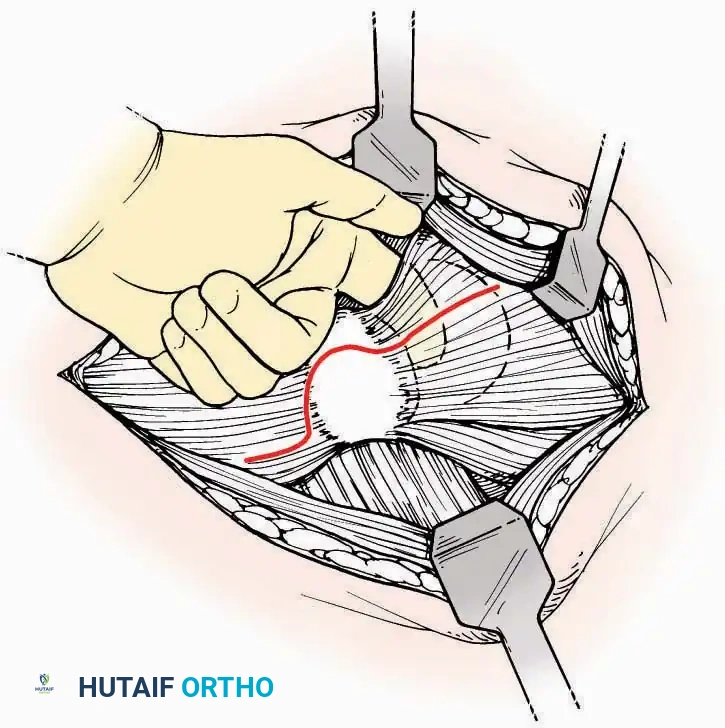

Anterior Approach

Indications: Total ankle arthroplasty (TAA), anterior ankle arthrodesis, and excision of anterior tibial/talar osteophytes (anterior impingement).

💡 Clinical Pearl

Gaining access to the medial gutter (the articulation between the medial malleolus and the medial articular facet of the talus) can be challenging through a pure anterior approach. Meticulous medial subperiosteal dissection of the joint capsule is required to avoid excessive traction on the anterior neurovascular bundle.

Surgical Technique:

* Incision: Make a 10 to 15 cm longitudinal incision over the anterior aspect of the ankle, centered exactly midway between the medial and lateral malleoli.

* Superficial Dissection: Incise the superficial fascia. Identify and protect the superficial peroneal nerve branches laterally and the saphenous nerve medially.

* Internervous Plane: The deep dissection exploits the plane between the Extensor Hallucis Longus (EHL) tendon (innervated by the deep peroneal nerve) and the Extensor Digitorum Longus (EDL) tendons (also innervated by the deep peroneal nerve).

* Neurovascular Bundle: Incise the extensor retinaculum. Carefully identify the anterior tibial artery and the deep peroneal nerve, which typically lie between the EHL and EDL, or directly deep to the EHL. Retract the neurovascular bundle laterally with the EDL, or medially with the EHL, depending on the specific anatomical variant encountered (lateral retraction is most common).

* Capsulotomy: Incise the anterior joint capsule longitudinally. Elevate the capsule subperiosteally from the anterior tibia and the talar neck to expose the entire tibiotalar articulation.